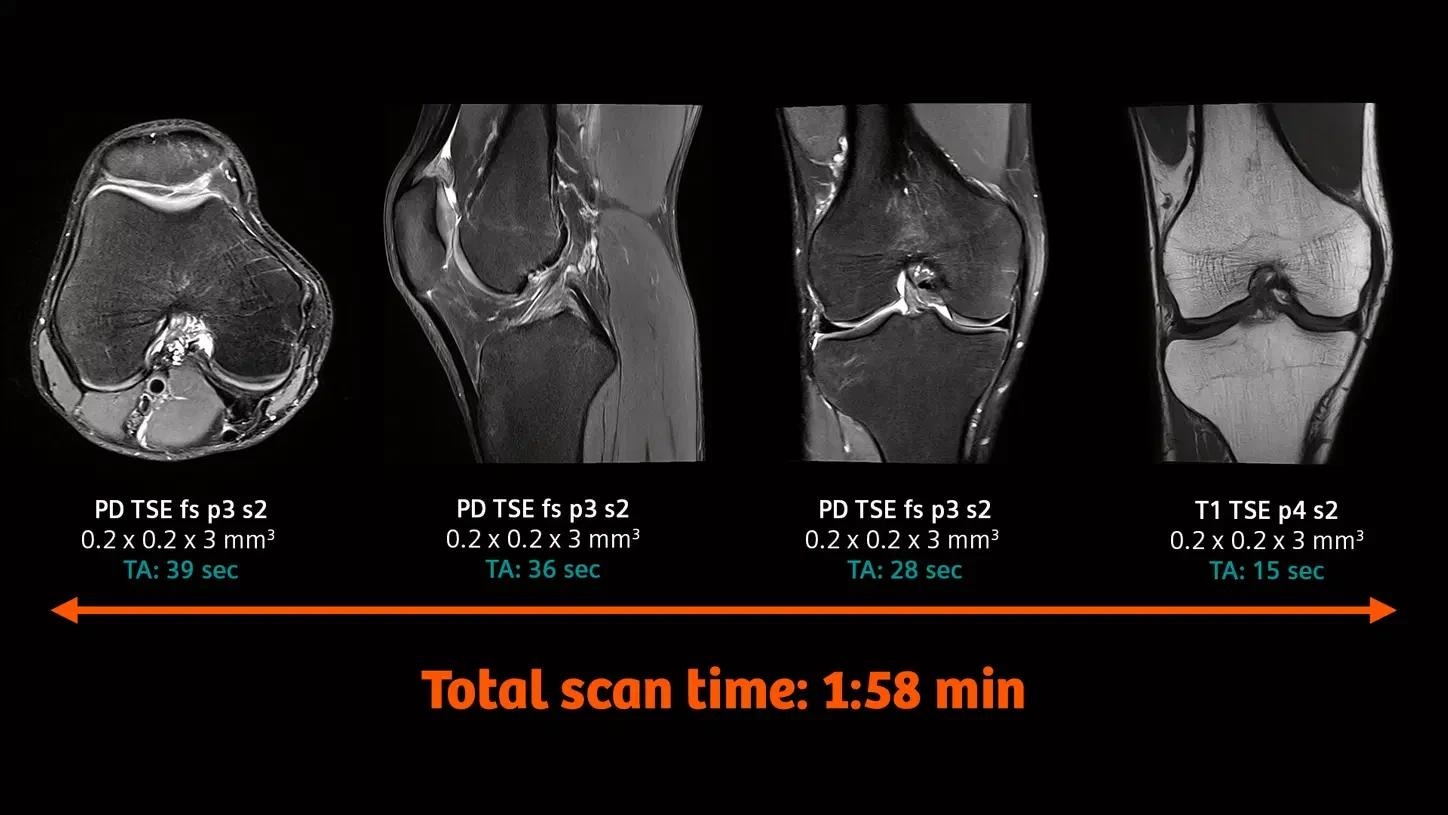

MSK

Orthopedics

Knee imaging with the new Tx/Rx Knee 18

The new coil provides high-resolution knee imaging as well as a wider coil aperture to accommodate a larger patient population.

Image Credit: University Hospital Tübingen, Germany